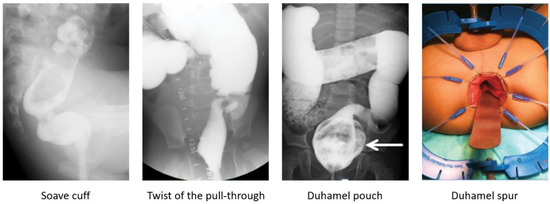

A contrast enema helps to reveal a mechanical obstruction resulting from an anastomotic stricture, obstructing Yancey–Soave cuff, a twist of the pull-through segment, or a Duhamel spur or pouch (Figure 2) [3,39,44]. A rectal biopsy rules out a transition zone pull-through [3,7]. The anatomic causes of obstruction require surgical correction [3,39,44]. An obstructive Soave cuff, a twist of the pull-through, and a mega Duhamel pouch indicate a redo pull-through with the resection of the abnormal colonic segment. A Duhamel spur can be managed with the use of an endovascular stapler to create a common channel between the spur and colon lumen. Should this intervention fail to improve obstructive symptoms, a redo pull-through should be performed [45]. Very short refractory distal strictures can be corrected with a Heineke–Mikulicz technique while a redo pull-through is required for more severe cases.

Figure 2. Anatomic causes of obstruction revealed on a contrast enema or examination under anesthesia and requiring surgical correction.